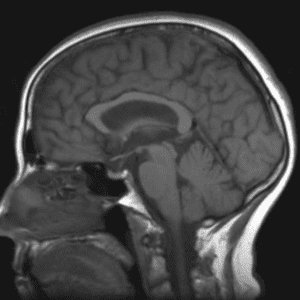

Case #15

Tectal glioma